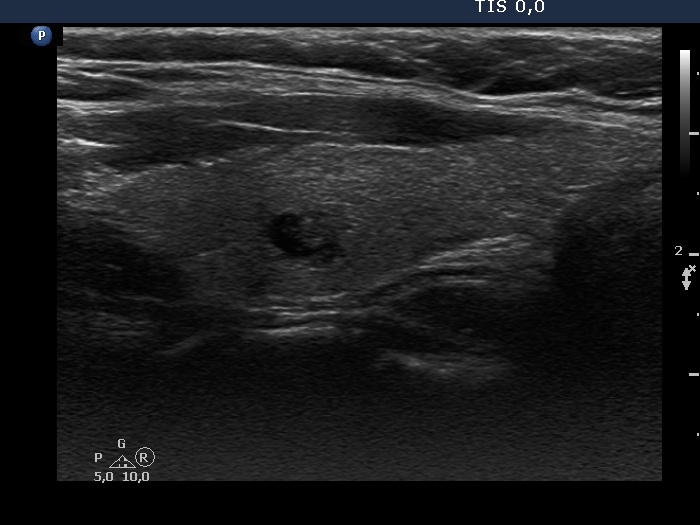

Consecutive patients with the final diagnosis of Hashimoto's thyroiditis - case 22 (285) (ultrasonographic picture 5)

Left lobe, longitudinal scan. The deeply hypoechogenic area seems to be a cystic lesion on this view.